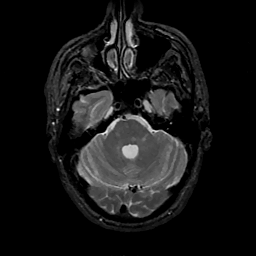

MR Study #11, May 5, 1991 -- Slice #13

[Home][Help][Clinical][Tour 1][Tour 2] Slice 13